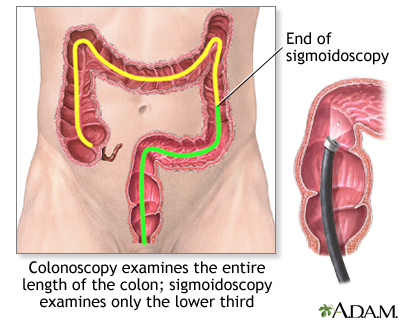

Sigmoidoscopy using a flexible scope is a procedure used to see inside the sigmoid colon and rectum. The sigmoid colon is the area of the large intestine nearest to the rectum and is about one third of the total colon.

- Next, the flexible sigmoidoscope is placed through the anus. The scope is a flexible tube with a camera at its end. The scope is gently moved into your colon. Air or carbon dioxide is inserted into the colon to enlarge the area and help the provider view the area better. The air may cause the urge to have a bowel movement or pass gas. Suction may be used to remove fluid or stool.

Sigmoidoscopy using a rigid scope may be done to treat problems of the anus or rectum but is not used to screen for colon cancer.